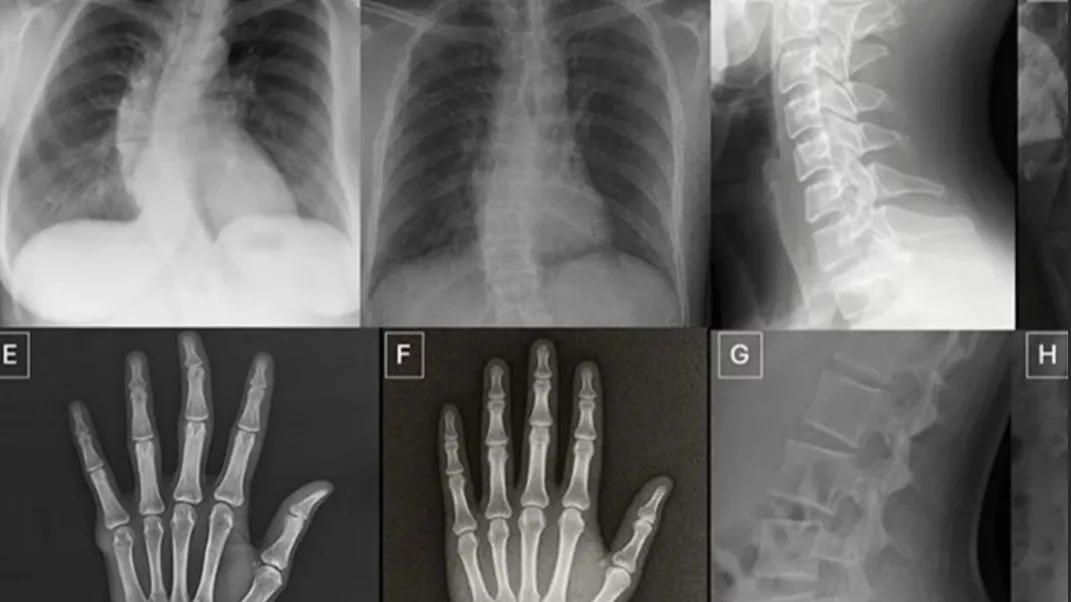

Un reciente estudio publicado en la revista Radiology de la Radiological Society of North America (RSNA) encontró que las imágenes de rayos X generadas por inteligencia artificial son tan realistas que incluso radiólogos entrenados tienen dificultades para distinguirlas de las auténticas.

La investigación, liderada por el Dr. Mickael Tordjman y su equipo de la Icahn School of Medicine del Mount Sinai (Nueva York), evaluó la capacidad de 17 radiólogos de seis países para identificar imágenes médicas sintéticas en un conjunto de 264 radiografías. La mitad de las imágenes eran reales y la otra mitad había sido generada por modelos de IA como ChatGPT‑4o y RoentGen, un sistema especializado en crear radiografías sintéticas.

Para Tordjman, estas limitaciones no son un obstáculo menor: “las imágenes médicas falsas suelen verse demasiado perfectas —huesos excesivamente lisos, columnas vertebrales inusualmente rectas, pulmones excesivamente simétricos— y pueden pasar desapercibidas incluso para ojos expertos”, según explicó.